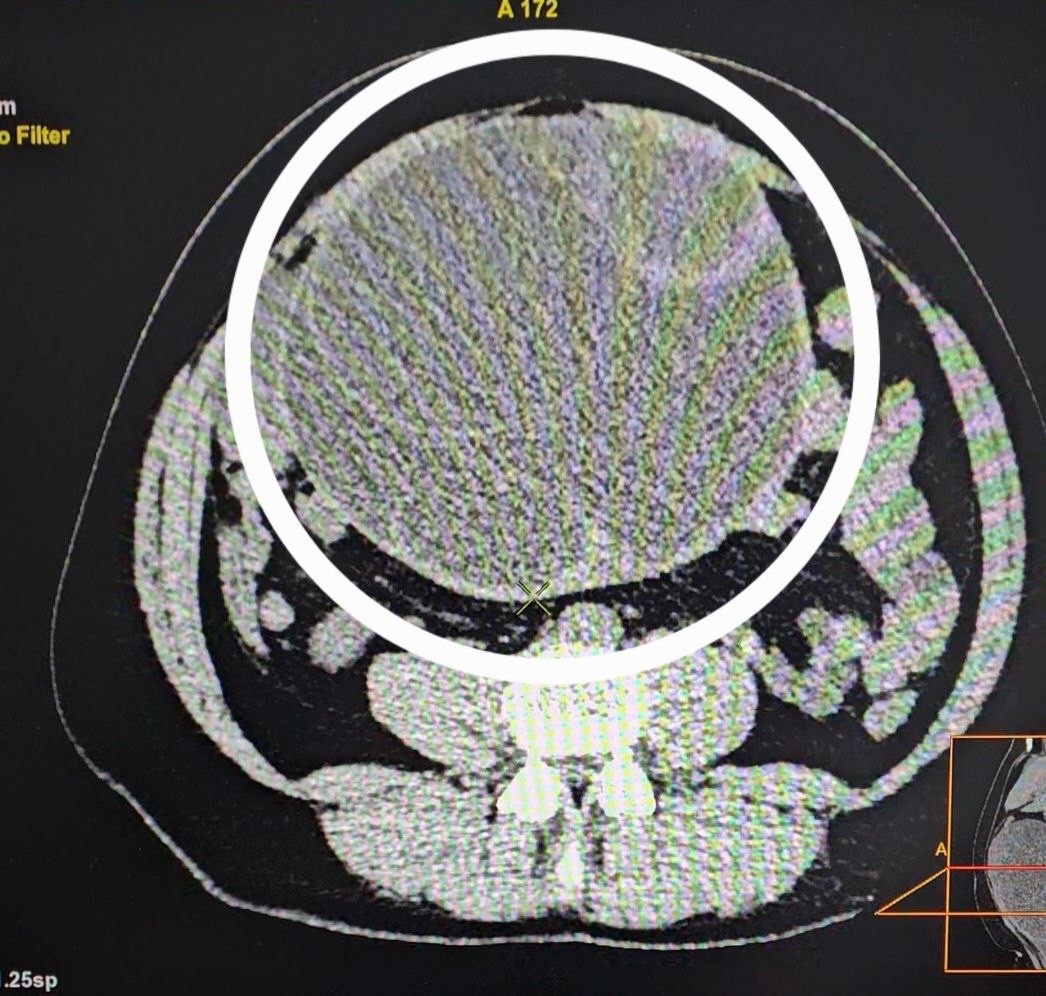

Обратиться к врачам женщина решила, когда начала испытывать сильную боль. Во время осмотра врачи обнаружили опухоль, наличие которой потом подтвердила КТ.